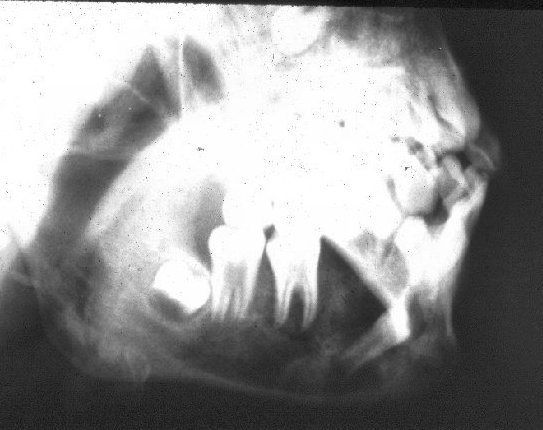

- Ακτινογραφικά ευρήματα: Διαύγαση με ασαφή και δυσδιάκριτα όρια, λύση ή διάτρηση των συμπαγών πετάλων, παρεκτόπιση των εμπλεκομένων δοντιών και ορισμένες φορές υποπεριοστική εναπόθεση οστού με τη μορφή των ακτίνων ήλιου.